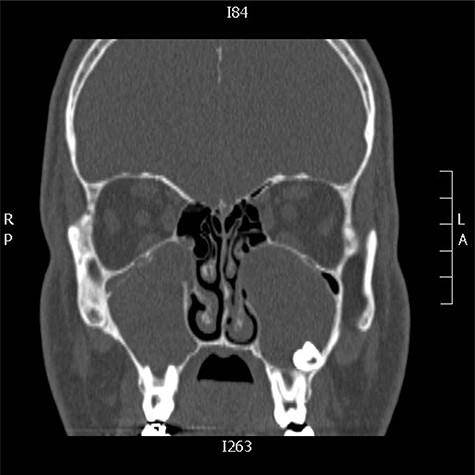

A 19-years-old male presented to otolaryngology clinic facial pain over the upper jaw area along with post-nasal discharge for 6 months. Patient gave history of recurrent sinusitis; otherwise, he is medically and surgically free with no history of trauma. Examination showed septal spur to the left side with no other significant findings. CT scan of the paranasal sinuses showed bilateral ectopic teeth and cystic lesions within both of the maxillary sinuses (Fig. 5). Patient was managed with endoscopic endonasal enucleation of the cysts and extraction of the ectopic impacted teeth through middle meatal antrostomies. Histopathology confirms the diagnosis of dentigerous cysts. Post operatively, the patient symptoms resolve completely, and she remained symptoms free over 5 years follow up.

CT scan of the paranasal sinuses showed bilateral ectopic teeth and cystic lesions within both of the maxillary sinuses.